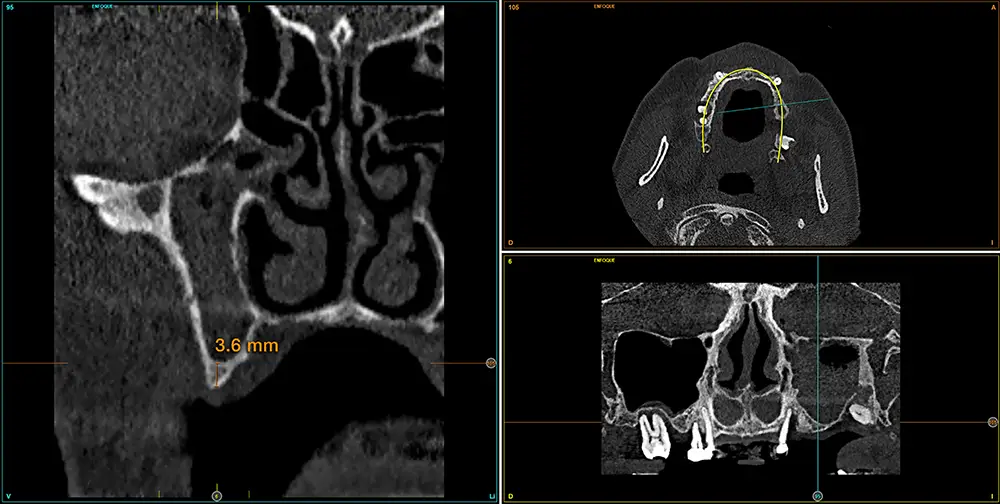

Para realizar una planificación precisa del caso y determinar el volumen óseo residual antes de la cirugía implantológica, se realiza un estudio mediante tomografía de haz cónico (cone-beam) y se visualiza mediante un software específico (BTI-Scan IV). Esta exploración permite medir con exactitud la altura y anchura de la cresta ósea, así como evaluar la densidad de las zonas en las que se prevé colocar los implantes, facilitando así una planificación quirúrgica fiable y ajustada a las necesidades anatómicas del paciente44–47. En las imágenes del cone-beam de control, observamos en el segundo cuadrante una atrofia vertical extrema, con zonas de menos de 4 mm de altura, donde se planifican implantes de 4,5 mm de longitud que serán colocados mediante el procedimiento de elevación transcrestal con fresa de corte frontal y con hueso autólogo obtenido del fresado embebido en PRGF-Endoret como material de injerto. Esta técnica, descrita por nuestro grupo de estudio, nos permite realizar un abordaje seguro del seno maxilar con una escasa invasividad (figs. 8-10)9,25,29,36.

Figs. 9-10. Medida de la zona con mayor atrofia del segundo cuadrante menor a 4 mm de altura y planificación del implante de 4,5 mm de longitud que será colocado mediante el procedimiento de elevación transcrestal anteriormente descrito.

En la zona correspondiente a la pieza 24, tenemos una atrofia extrema también pero en este caso en sentido vertical, con una cresta residual de 3,1 mm de grosor, como podemos ver en el corte seccional del cone-beam (fig. 11). En este caso se planifica la colocación de un implante de 2,5 mm de diámetro y 6,5 mm de longitud (con plataforma reducida de 3 mm -plataforma 3.0, biotechnology institute-) (fig. 12). Igualmente, en la zona anterior de la premaxila, tenemos una situación muy similar donde el volumen óseo es reducido, incluso más que en la zona del segundo cuadrante y, por ello, optamos también por implantes de 2,5 mm de anchura y plataforma de 3 mm (figs. 13-16).

Fig. 11. Corte de planificación de la zona correspondiente a la pieza 24, que presenta una atrofia ósea en anchura extrema con 3,1 mm de anchura residual.

Fig. 12. Planificación del implante de 2,5 mm de diámetro y 6,5 mm de longitud que será colocado en la zona.